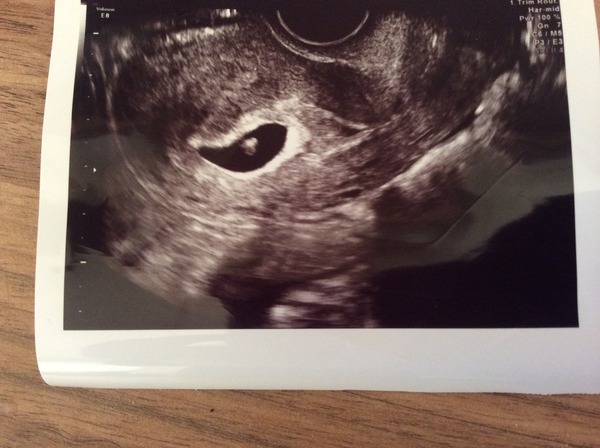

Here's blob Smileim worried about the dates not matching up but hopefully be ok.

alien Aww, lovely pic. Sweet little worm.

spam oh that nice to hear someone else having same thing! that's the disadvantage of early scans I guess. The lady said I may have ovulated much later than normal. Keep thinking baby is small but she said it's not as if it wasn't right size for dates it would have a slower heartbeat and other characteristics but it has a super strong heartbeat so all normal.

Aaaah lovely photo Alien Grin. I know the date difference is going to niggle at you but a heartbeat is a heart beat and just finding one takes your miscarriage stats way low. Maybe try and have another scan at 9 weeks and put your mind at rest that everything is on track week wise.